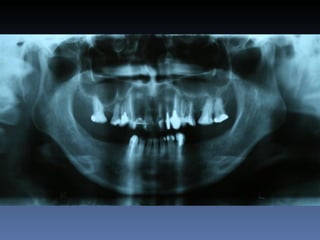

Dominga Maria silva

Idade – 53 anos

Sexo – Feminino

Raça – Caucasiana

ASA – II

Data- 23-04-2012

Diagnóstico:Desdentada parcial maxila

Plano de tratamento:      Reabilitação com 6 blocos

“onlay” provenientes de Úmero fresco-congelado

(FFB); reabertura para instalação de 6 implantes

dentários endo-ósseos e reabilitação protética fixa.

Zona    Zona    Zona   Zona    Zona     Zona

1.6    1.3     1.1     2.1     2.3      2.6

Stage I       2,0mm   1,5mm 1,5mm 2,9mm 1,5mm         1,5mm

Pré-op (mm)

Stage I     6,5mm     7,0mm 7,1mm 5,2mm 6,7mm         7,0mm

Pós-op (mm)

Aument        4,5mm   5,5mm   5,6mm   2,3mm   5,2mm   5,5mm

o

Espessura

(mm)

Reabert       6,4mm   7,0mm   7,0mm 5,1mm     6,6mm   7,0mm

ura

Stage II

Reabsor       0,1mm   0,0mm   0,1mm   0,1mm   0,1mm   0,0mm

ção